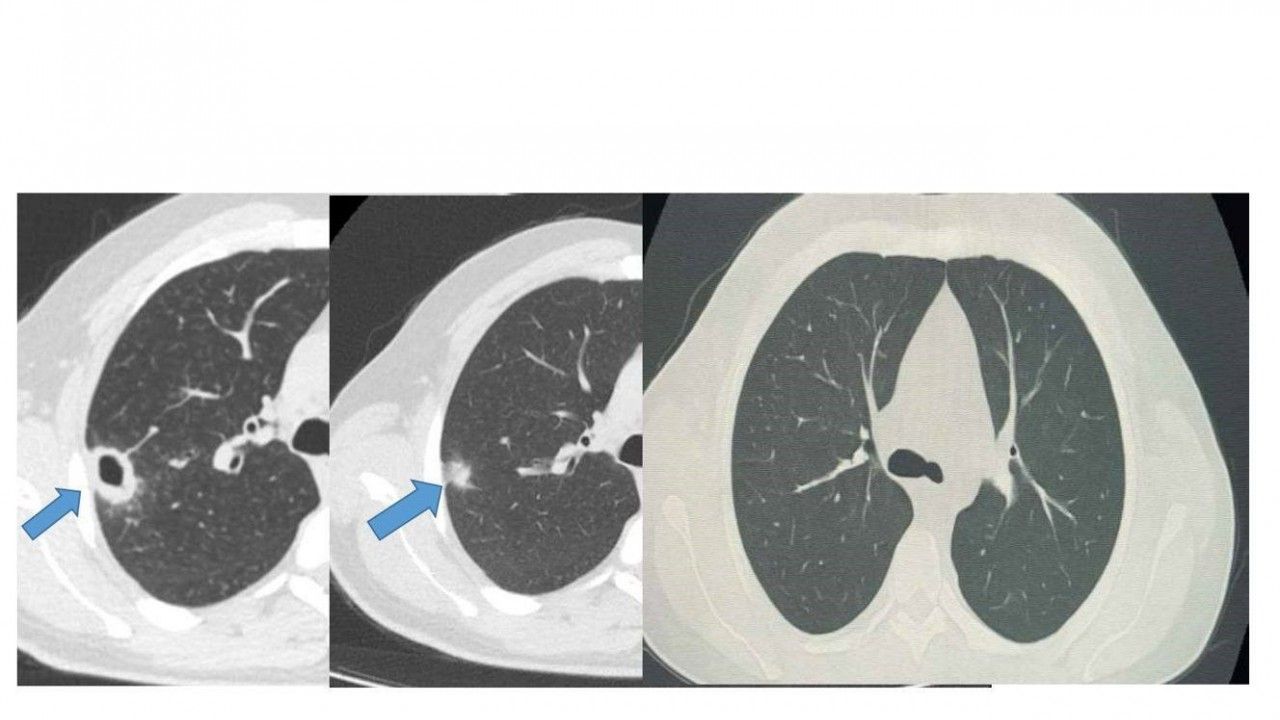

Bayburt Devlet Hastanesine öksürük ve balgam şikayetiyle başvuran 50 yaşındaki hastanın akciğerinde kitle benzeri bir doku tespit edildi. Yapılan tetkikler sonucu ciddi bir hastalık olmadığı belirlenen hasta, erken tanı ve doğru tedavi sayesinde sağlığına kavuştu.

Göğüs Hastalıkları Uzmanı Uzm. Dr. Hilal Sayma tarafından muayene edilen hastaya ileri tetkik amacıyla bronkoskopi işlemi uygulandı. Bronkoskopi sonucunda lezyonun kanser veya tüberküloz gibi ciddi hastalıklarla ilişkili olmadığı belirlenerek, hasta için uygun tedaviye başlandı.

İki haftalık tedavi sürecinin sonunda yapılan kontrollerde lezyonun neredeyse tamamen gerilediği görüldü. Sağlığına kavuşan hastanın taburcu edildiği ve durumunun iyi olduğu öğrenildi.